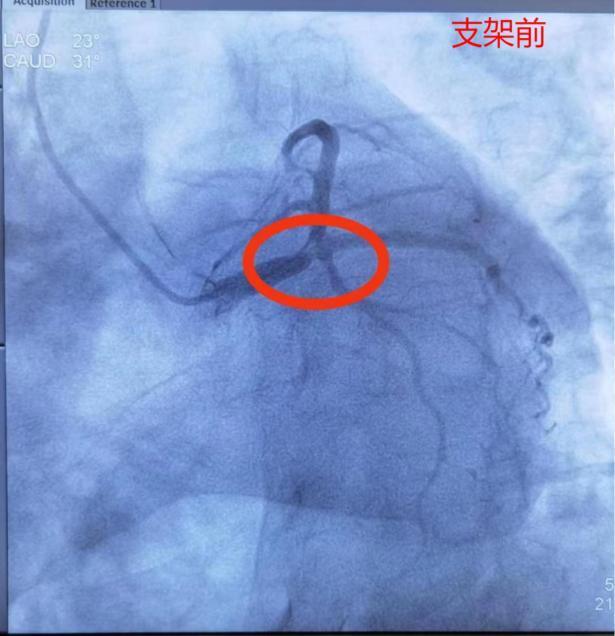

紧急与家属沟通,在征得患者家属同意后,17:10汤先生由急诊科送入导管室行紧急PCI术。冠脉造影显示:左主于末端85%-90%重度狭窄,前降支开口90%重度狭窄,局部可见明显血栓影。从进入导管室到手术结束,前后约45分钟,门球时间50分钟。术后汤先生生命体征平稳、转危为安。

汤先生X线透视下心脏跳动微弱,造影示左主干重度狭窄、可见明显血栓、前降支TIMI血流2级,考虑为左主干闭塞后再通,否则病人没有机会达到医院。再次提醒大家,发生胸闷胸痛症状,一定要及时就医,不要错过最佳抢救时机。

对于急性心肌梗死患者来说:“时间就是心肌、时间就是生命!”急诊造影并支架植入治疗(PCI)是目前救治这种类型急性心肌梗死的首选治疗方式,并且越早治疗,获益越大。PCI能够尽快开通闭塞段血管,缩小心肌梗死面积,挽救缺血的心肌细胞,拯救生命,对提高患者存活率、降低死亡率和致残率都有重要意义。